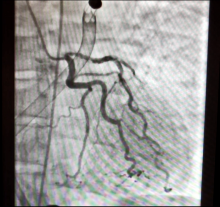

Right Pulmonary Endarterectomy

The right pulmonary artery was approached, medial to the superior vena cava. After the patient was cooled to 20°C, the aorta was cross-clamped and a single dose of Custodiol-HTK cardioplegic solution was administered. An incision was made in the right pulmonary artery and carried past the take-off of the middle lobe artery. Circulatory arrest was then initiated. An olive tip suction instrument was used to develop a thromboendarterectomy plane. The thromboendarterectomy extended into the subsegmental vessels. Once the right-sided thromboendarterectomy was completed, circulation was restarted and the arteriotomy was repaired using a pericardial patch with a continuous 6-0 polypropylene suture. The total circulatory arrest time was 15 minutes.